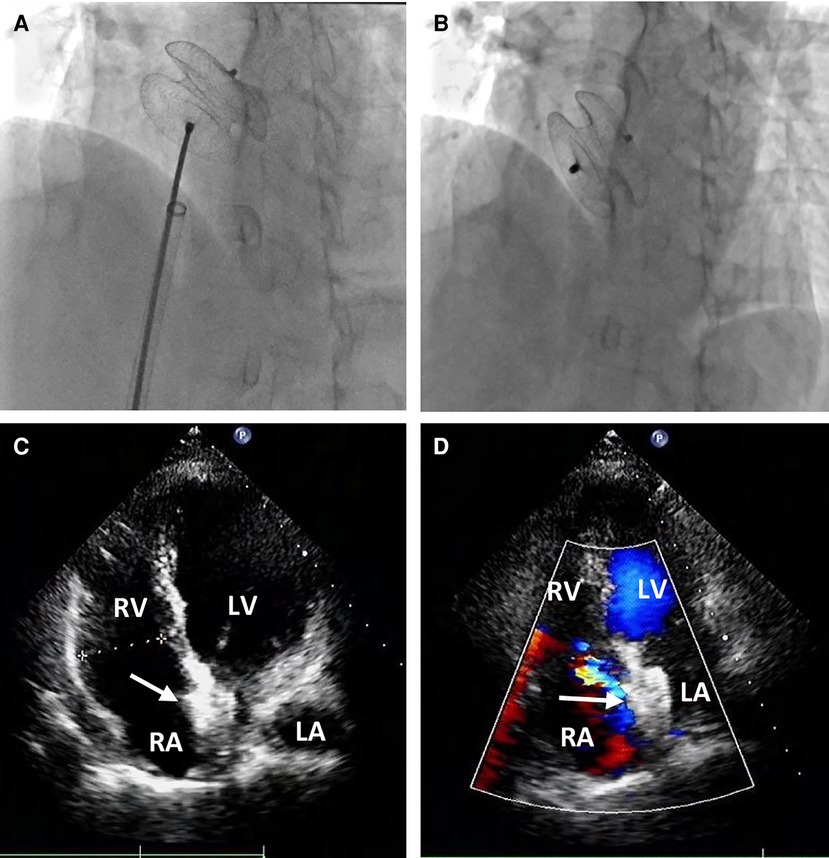

A 58-year-old asymptomatic woman residing in a remote countryside area was diagnosed with a secondary-type ASD during an evaluation for a heart murmur. Electrocardiography revealed a normal sinus rhythm with incomplete right bundle branch block. Local transthoracic echocardiography demonstrated a delicate and weak area measuring approximately 22 mm in the middle of the atrial septum, exhibiting movement synchronized with the cardiac cycle and abnormal left-to-right shunt flow, along with mild dilation of the right ventricle and atrium (Figure 1A). The physical examination revealed no contraindications for percutaneous closure. The intraoperative fluoroscopy confirmed the findings, as the guidewire sequentially passed through the inferior vena cava, right atrium, and defect site to the left atrium (Figure 1B). Given the delicate and weak area in the middle of the atrial septum, a 24 mm ASO device was successfully deployed under fluoroscopic guidance. The position of the occluder device was optimal, with no residual shunt observed on fluoroscopic examination after the final release (Figure 1C, arrow). However, two days after implantation, a heart murmur reemerged, and immediate transthoracic echocardiography revealed no occluder device in the middle of the atrial septum, accompanied by a significant left-to-right shunt flow (Figure 2A). Chest x-ray indicated that the occluder was located in the descending aorta (Figure 2B). The patient was then referred to our cardiac center. Computed tomography of the chest and abdomen confirmed the embolization of the occluder device to the descending thoracic aortic isthmus, with no evidence of vascular dissection, extravasation, or limb ischemia (Figures 2C,D). Since transthoracic echocardiography revealed no significant abnormalities in the anatomy and function of the mitral and aortic valves, and there were no significant hemodynamic changes, the patient underwent percutaneous retrieval of the embolized occluder device and subsequent redeployment under local anesthesia (Figure 3).

Figure 1. Secundum-type ASD finding and percutaneous secundum-type ASD closure. Transthoracic echocardiography revealed about 22 mm ASD (white arrow) with shunt flow from left atrium to right atrium (A) The intraoperative fluoroscopy showed that the guidewire passed through the inferior vena cava and the right atrium sequentially, and then through the defect site to the left atrium (B); a 24 mm ASO device was successfully deployed in the ASD (C).